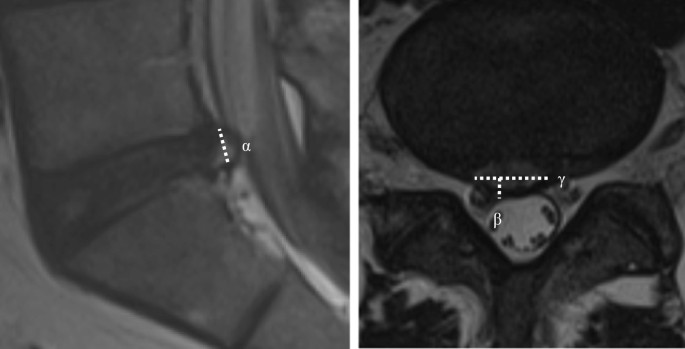

Demographic data, such as age, sex, body mass index, and clinical baseline characteristics, such as past medical history, preoperative duration of symptom, previous history of nerve block, trauma history, and symptom dominance (low back pain or radiating leg pain) were assessed between the two groups. In addition, preoperative magnetic resonance imaging (MRI) findings, such as degree of disc degeneration and degree of herniation, were evaluated between the two groups. The volume of disc herniation was determined as transverse diameter × depth × height of disc herniation × 1/2 (mm3) (Fig. 2).